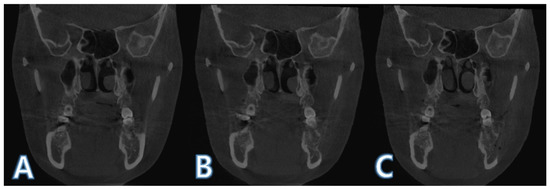

2.2. Boundary Selection of Region of Interest and Mandible Segmentation

2.3. Intensity-Based Registsration Using Segmented Mandible

2.5. ROI Image Acquisition and Boundary Separation

2.6. ROI Volume and Mean Pixel Value Calculation